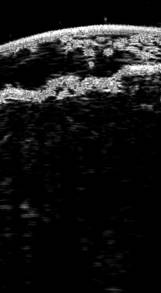

Правая голень значительно увеличена в окружности, отечна, с выраженными явлениями лимфостаза, на фоне которого расположен циркулярно охватывающий очаг поражения неправильной формы с четкими границами, на передней поверхности распространяющийся на область коленного сустава, сзади заканчивающийся в подколенной ямке, переходящий на кожу голеностопного сустава и проксимальных отделов правой стопы, цвета свежего мяса, с опухолевидными узлами диаметром до 1,5 см и папилломатозными разрастаниями тестоватой консистенции, выступающими над уровнем непораженной кожи на 1,0 см. В бороздках между ними определяется значительное количество густого липкого экссудата и мацерация, некоторые ворсинки покрыты плотными гиперкератотическими наслоениями грязно-серого цвета (рис. 1). По периферии очага отмечаются ободок гиперемии с цианотичным оттенком и остаточные явления псориатических высыпаний в виде инфильтрированного участка с чешуйками серебристо-белого цвета на поверхности.

Рис. 1. Клиническая картина на момент поступления больного в стационар